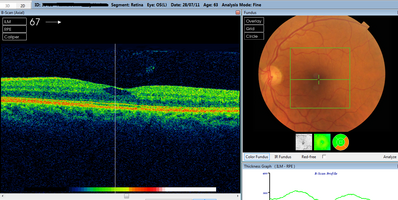

OCT scan

Can anyone help me identify what this is? Is it a resolving hole? Macular tear? Just fluid?

Macula, hole, tear, OCT